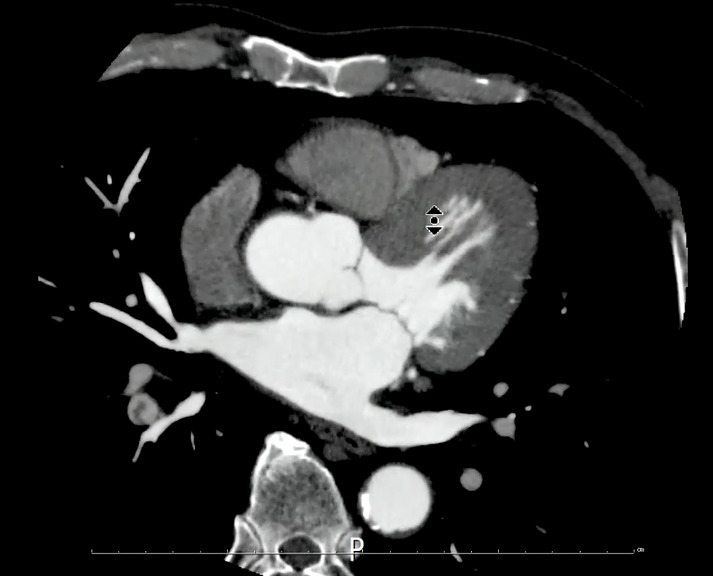

その時の画像がこちらです。

造影後3分で追加撮影をしました。

この方は検査前情報にはなかったのですが、右のTKA術後の方でした。右膝関節術部周囲を主体に下腿~大腿骨遠位レベルにfilling defectが複数認められました。

管電圧を下げて撮影することで、造影剤が60mlほどでも深部静脈の評価が可能でした。時間経過で造影効果が低くなった肺動脈の観察も観察することができました。

現場で症例に気づき、寝台から降ろさずに放射線科に相談し腎機能低下していることから追加造影は行わずに管電圧を低くして撮影に対応し、病変部が観察できた症例になります。